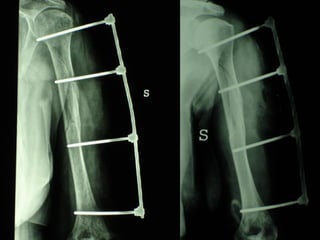

INDICAZIONI COMUNI Fratture sovracondiloidee Fratture intercondiliodee Fratture diafisarie distali PARTICOLARI Fratture con grave osteoporosi Fratture periprotesiche

VANTAGGI CHIRURGIA MININVASIVA Mini Open Inserimento della placca sottocutaneo per scivolamento Viti percutanee Preservazione dei tessuti molli Ridotto danno vascolare Rapida ripresa funzionale

LISS  NCB

NCB

Conclusioni Riduzione  anatomica Minimo trauma chirurgico Corretto equilibrio fra elasticità e stabilità Precoce mobilizzazione